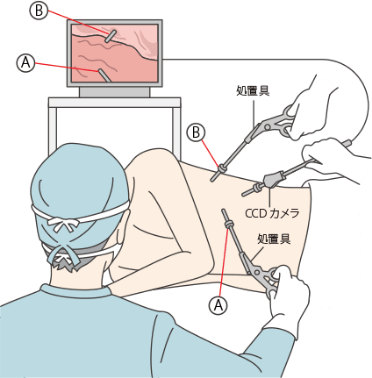

手術も可能な胸腔鏡

肺の組織が収まっている胸腔というところに内視鏡を挿入し、組織採取や手術を行うものです。胸腔の中に内視鏡を入れておこなう検査を胸腔鏡検査といいます。胸腔鏡検査は気管支鏡検査で診断がつかないときにおこなわれることがあります。全身麻酔をかけておこなう手術の一種と考えたほうがよいでしょう。

通常は皮膚3箇所を1cmくらい切開し、1箇所からカメラを、他の2 箇所からメスや鉗子などの手術具を挿入して処置や検査、手術をおこないます。通常の大きく胸を切開して行う手術に比べると、切開する傷が小さいので、患者さんの体の負担は少なくてすみます。

その一方で、カメラの画像を見ながらの処置・手術となるため術視野が狭く、立体感が乏しいことから、手技は難しくなります。したがって、胸腔鏡の処置・手術中に何か危険が発生した場合に、通常の胸部手術に切り替えて、胸を大きく切開することもあります。

最近では胸水の検査目的などで胸腔鏡を、局所麻酔をかけて行うこともあります。ただしその場合は、肺の一部を切除するような大きな処置は行わないのが普通です。